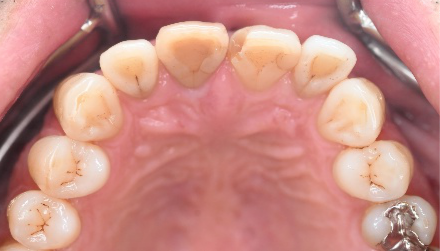

女性 Aさん 50代 (セラミックインレー)

主訴

左上の銀歯2本を白くしたい。

治療内容

銀歯を取り除き、セラミックインレーをいれました。

所感

患者さんは、お口の中の金属を徐々に取り除くことを希望され、今回は左上の奥歯2本をセラミックに替え、ノンメタルにしました。体全体の健康を考えると正しい選択だと思います。

セラミックインレー2本:¥52,800×2本=¥105,600(税込)